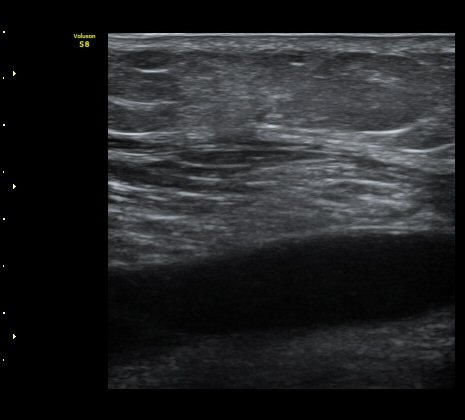

³»Ãøºñº¹±Ù°ú °¡Àڹ̱٠»çÀ̰¡ ¹ú¾îÁö°í ¼ö¾×ÀÌ Àú·ùµÊ.

ÃÊÀ½ÆÄ À¯µµÇÏ ¼ö¾× ÈíÀÎ(÷ºÎ µ¿¿µ»ó) ÈÄ ¾Ð¹ÚºØ´ë °íÁ¤.